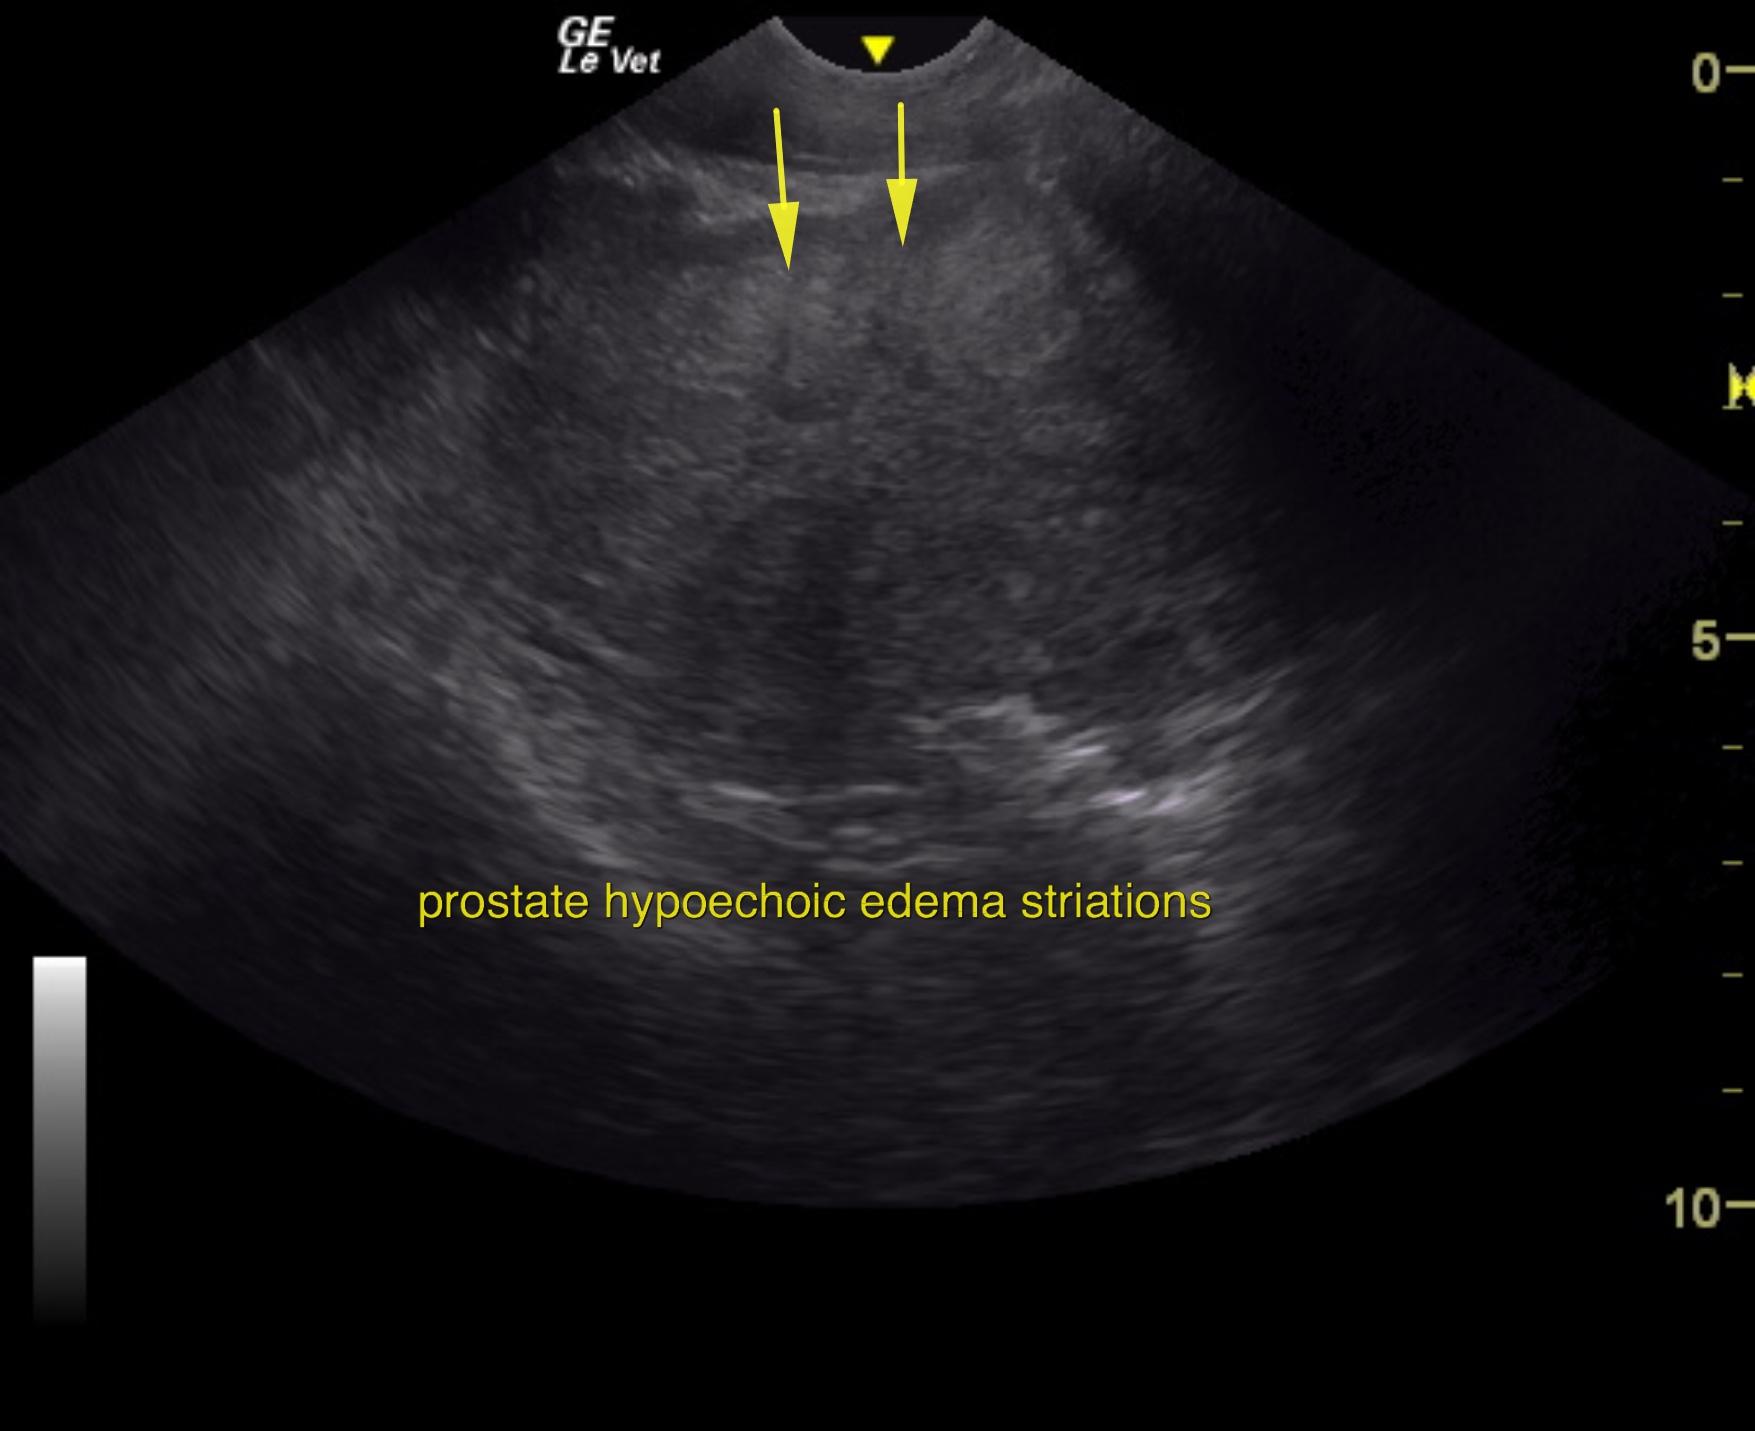

An 11-year-old NM Labrador with a history of gradual weight loss was presented for evaluation of abdominal pain and diarrhea. On abdominal palpation, the intestines were gas-filled, which was confirmed on survey radiographs. Elevated ALT activity, BUN, and glucose were present on serum biochemistry.